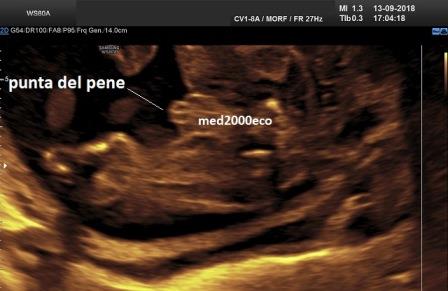

Diagnosi ecografica prenatale

La diagnosi ecografica prenatale è solo di sospetto. Le caratteristiche ecografiche prenatali possono essere caratterizzate da: